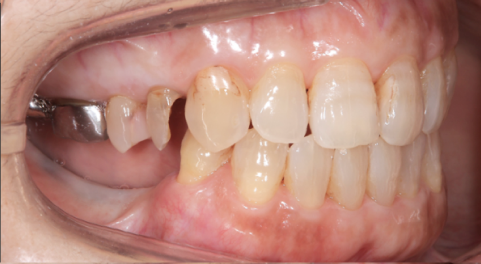

外れた左下の歯ですが、歯茎から出ている歯の部分が明らかに短く、この状態で被せ直しをしても維持力がないためすぐに外れてしまう事が予想されました。

また、奥歯がないためこの歯には噛む時の力が過剰にかかってしまいます。

この方の場合右の歯も少なく、主訴である左下の歯だけ治療をしたとしても今残っている歯も含めてどんどん悪くなることが予想されました。

このような理由で口腔全体を含めた「全顎の治療」計画を提案させていただきました。

現状残っている歯の状態から、この患者さまは「生理的咬合」であると診断し、現状噛んでいる歯の位置の修正とは行わずに、歯がないところ、歯が欠けているところを治すだけで安定すると考え治療を行っています。

この歯(黄色の印)は顎を横に動かした時に強い力が加わり、歯の周囲の組織にダメージが出ているため、力をコントロールするために歯の形を修正が必要です。